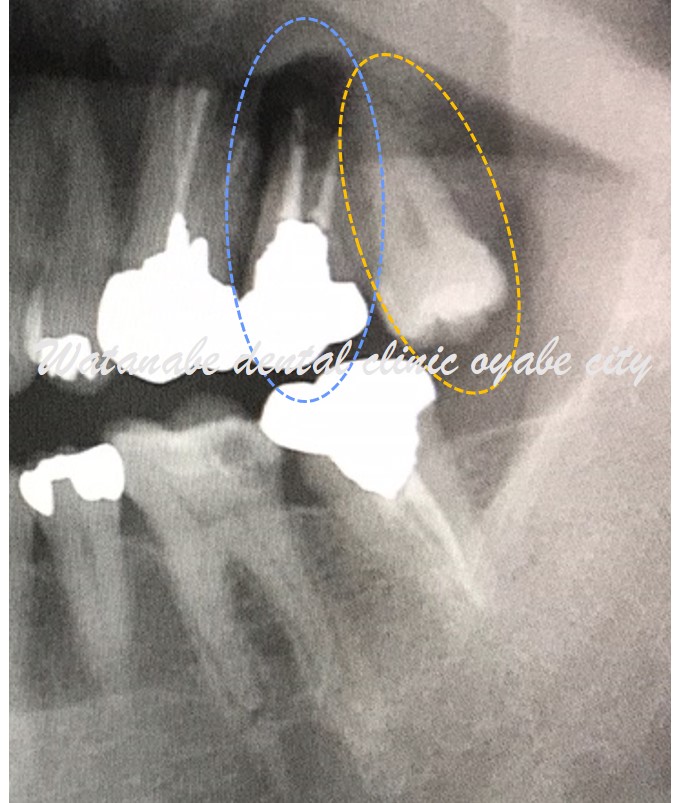

下写真の青〇の歯は歯根が折れていて抜歯となります。その隣にオレンジ〇の親知らずがあるため、青〇の歯を抜歯してオレンジ〇の親知らずを移植する計画としました。